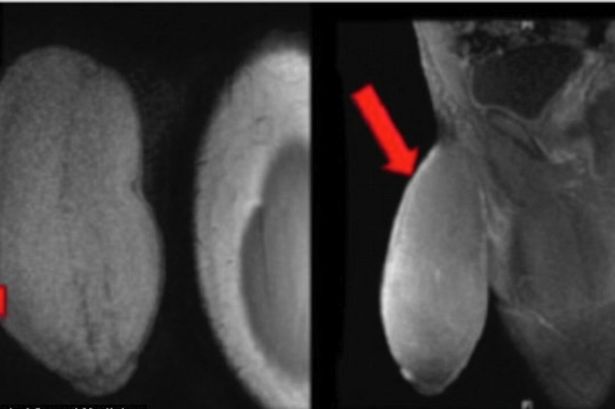

外科医のキャリオン氏はその話を聞いた時に、少なからぬショックを受けた。計測したところ、弛緩した状態で長さは約17.78センチ、その円周は約25.4センチ、グレープフルーツほどの大きさだ。形状としてはアメリカンフットボールのような形をしているそう。

キャリオン医師はそう語る。少年には持続勃○症のいくつかの症状が見られ、勃○の状態になっても大きくなることは無く、ただ硬くなるだけだったという。彼はスポーツ競技などで普通のサイズのユニホームを着用するとあまりに目立つのが恥ずかしく、活動することができなかったそうだ。

手術は無事成功し、家に帰るまでの入院していた2日間、少年は自分の新しい男根に「恍惚」としていたという。医師は最終的な計測はしていないが、「平均よりも少し長く、やや厚めですが、対称的で患者は満足していました。『美的な魅力がある。人生を変えるようなイベントでした』と満面の笑顔でしたよ」と語っている。